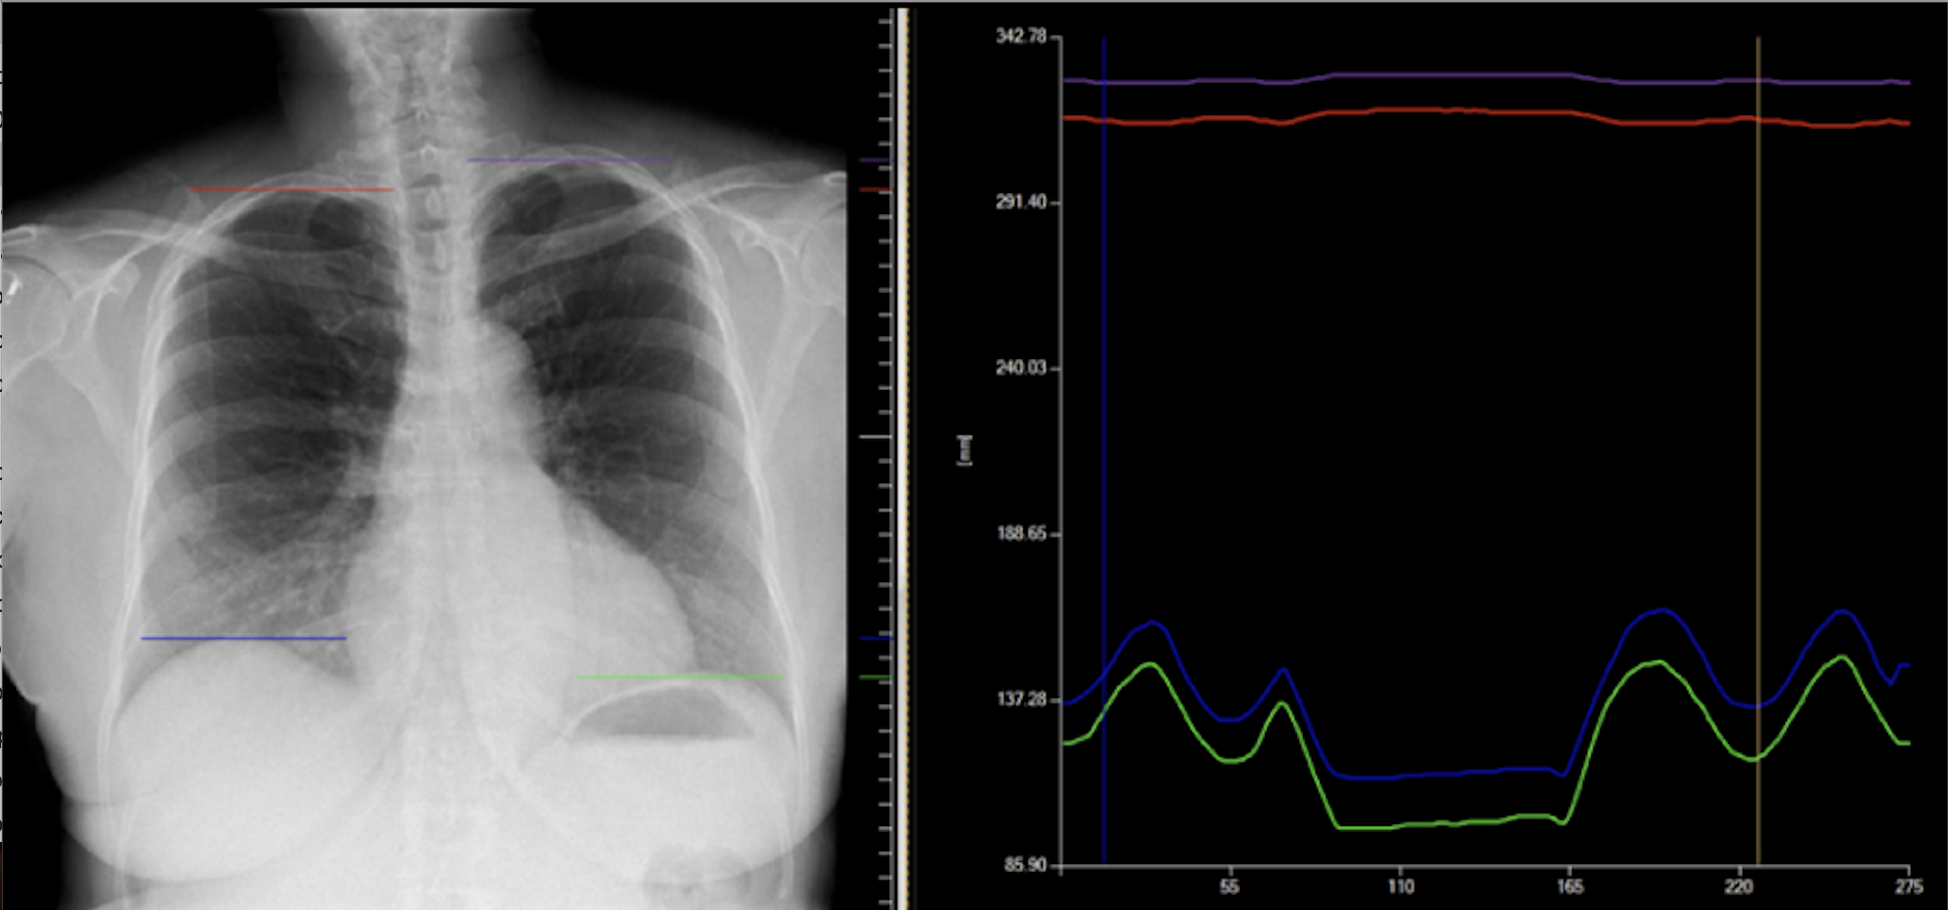

Konica Minolta's IWS workstation processes and quantifies Dynamic Digital Radiography diaphragmatic motion data.

DDR is a non-invasive cineradiography imaging technique that acquires up to 15 sequential radiographs per second and processes them as a cine loop, enabling clinicians to observe the physiological cycle as well as individual radiographs. This novel, low-dose advancement in digital X-ray enables visualization of anatomy in motion with a simple acquisition.